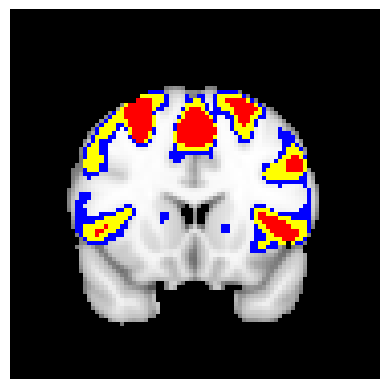

The confidence regions are constructed on fMRI scans from 77 subjects as a real data application of the proposed methods after applying additional smoothing with Gaussian kernel with FWHM to match the results shown in Bowring (2019) [BOWRING2019116187]. Confidence regions using 1) the joint method with , 2) the separate method with BH adjustment for upper and lower side each with , 3) the separate method with BH adjustment for upper side and two-stage adaptive procedure for lower with , and 4) SSS () were compared with threshold level 1.0%, 1.5%, and 2.0% Blood Oxygenation Level Dependent (BOLD) change. Joint control confidence regions are produced with instead of 0.05 for the reasons mentioned in chapter 3.

For all slices, FDR controlling methods show tighter inference of both upper and lower CR compared to the SSS method. SSS shows smaller upper CR and larger lower CR which suggests more conservative inference compared to FDR controlling testing based methodologies. This is due to the fact that by controlling for FDR, the method allows for more false discoveries in exchange for more discoveries in general. Despite having higher level at , joint control confidence regions still show comparable results to other methods even with higher significance level. Naturally, as the threshold goes up, the area enclosed between the upper and lower confidence regions decreases.

Confidence regions with separate controls of FDR for lower and upper are presented in two forms for comparison: one with BH procedure for the lower confidence region, and the other one with the two-stage adaptive procedure for the lower confidence region. The upper confidence region remains the same as both methods uses BH procedure for the upper set FDR control. Lower confidence regions with adaptive method are smaller than lower sets with BH procedure which is to be expected as the two-stage adaptive procedure is less conservative when more voxels are thought to be rejected. In the context of negative one-sided testing, this is equivalent to when there are less number of voxels above than below .